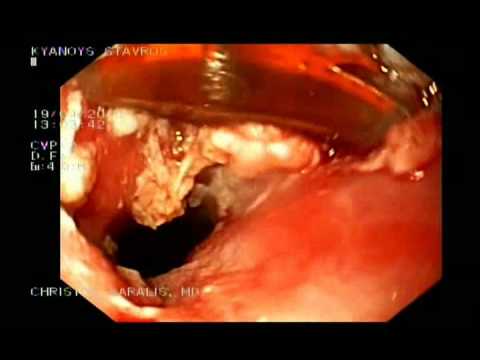

Plama Na Wejściu W Przełyku- Terapia Metodą Halo...

Wrodzone pozostałości śluzówki żołądka w przełyku, będące wynikiem nieprawidłowego rozwoju żołądka nazywane są przełykową "plamą na wejściu". Może ona występować u nawet 10% dorosłych. Czasami ze wzglęgu...